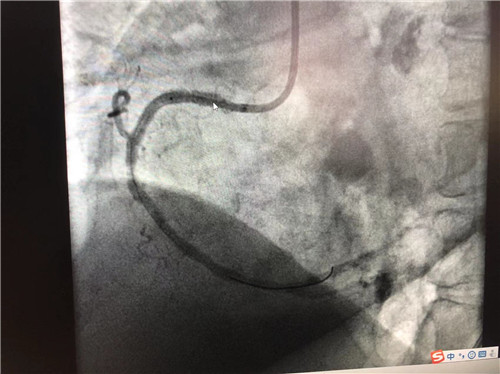

時間就是心肌,時間就是生命。導(dǎo)管室內(nèi),心血管內(nèi)科副主任徐先進、主任助理農(nóng)彥林已然待命,病人一到,團隊立即為其行深靜脈穿刺泵入血管活性藥物等,情況緩解后,行多體位冠狀動脈造影,確認RCA(右冠狀動脈)近端完全閉塞。經(jīng)家屬同意,在汪念東院長的指導(dǎo)下,徐先進、農(nóng)彥林、張星為患者行經(jīng)皮冠狀動脈球囊擴張成形術(shù)+經(jīng)外周靜脈穿刺中心靜脈置管術(shù)。術(shù)中,張奶奶再次出現(xiàn)室顫,心血管內(nèi)科團隊臨危不亂,立即予以300焦電除顫搶救,患者竇性心律恢復(fù)。隨后,球囊擴張為其置入心臟支架,復(fù)查造影顯示血管恢復(fù)暢通,無明顯夾層,殘余狹窄不到10%。術(shù)后,張奶奶血壓偏低,轉(zhuǎn)入ICU無創(chuàng)呼吸監(jiān)護,2天后轉(zhuǎn)回心血管內(nèi)科護理。

術(shù)后